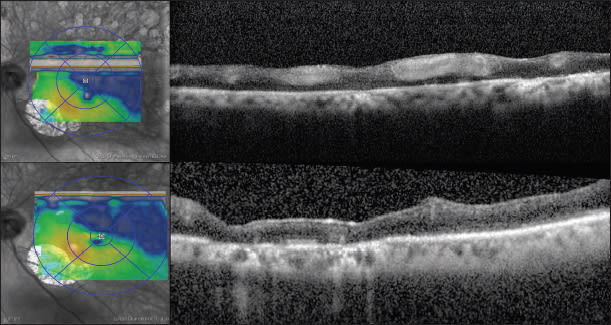

Her time-domain OCT showed CME, with a thickness greater than 500 µm (Figure 1, top). An intravitreal injection of bevacizumab was recommended at that time; however, the patient decided to wait, as she felt that her vision “hadn't changed much” with previous treatments.

Figure 1. Case 1: 65-year-old woman with macular edema due to CRVO. Time domain OCT demonstrating florid cystoid macular edema (top). Visual acuity was 20/60, and treatment was deferred by the patient. One month later, the visual acuity dropped to counting fingers, although the spectral domain OCT appearance was similar (bottom).

One month later, she returned for follow-up, complaining of decreased vision in the right eye. On examination, her VA had dropped to 20/400 in the right eye, despite a similar fundus and OCT appearance, although spectral-domain had replaced the time-domain OCT (Figure 1, bottom). At this point, she opted for the recommended treatment and had three monthly bevacizumab injections, before being enrolled in the Genentech Access Solutions program and receiving six consecutive monthly ranibizumab injections at reduced cost to her.

In November 2009, she presented with a visual acuity of counting fingers at two feet, with an SD-OCT appearance demonstrating persistent diffuse CME throughout the central macula (Figure 2, top). She received an intravitreal injection of dexamethasone (Ozurdex) and on follow-up OCT seven days later (per the package insert recommendations), her SD-OCT appearance was dramatically improved, with a visual acuity of 20/400 (Figure 2, bottom). On the most recent follow-up and after a total of 18 intravitreal anti-VEGF and two Ozurdex injections, with variable changes in her SD-OCT appearance, her VA remained counting fingers.

Figure 2. Case 1: SD-OCT shows diffuse CME throughout the central macula (top). Visual acuity was counting fingers. Seven days after an intravitreal injection of dexamethasone, SD-OCT was dramatically improved (bottom), with a visual acuity of 20/400.

A critical point of this case is that earlier treatment may have prevented the patient's visual loss, and OCT was not a sufficient method for gauging VA gain or duration of treatment effect. The appearance of OCT is similar in Figure 1 with greater than three lines of visual acuity difference; conversely, despite the fact that the retina regained a more physiologic appearance in Figure 2 after Ozurdex treatment, the visual acuity remained the same. The same treatment, instituted earlier, may have led to better long-term visual results. The patient's financial burden was obviously a factor in this case, but her loss of vision was certainly a high price to pay as well. Intravitreal drug manufacturer programs may be a vision-sparing option for such patients.